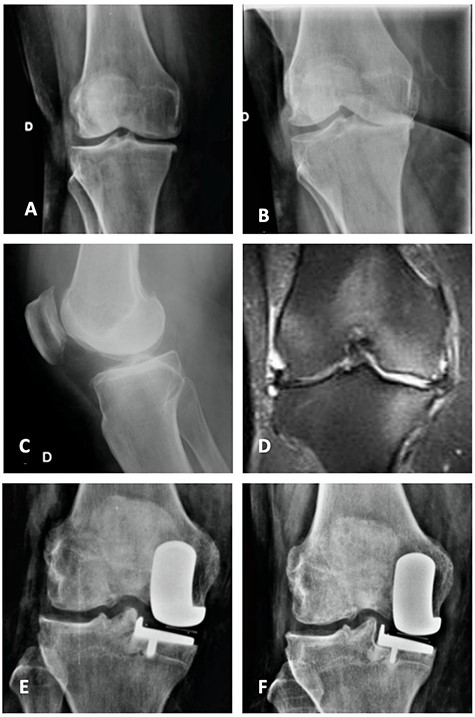

Orthostatic anterior view (A) and Rosenberg (B) X-ray images with medial osteoarthritis—right knee; Lateral view X-ray image of the same knee (C); T2 coronal MRI (D) with severe MP and femoral condyle SIFK; Immediate postoperative X-ray image (E) and 3 months after surgery (F) showing tibial component loosening.